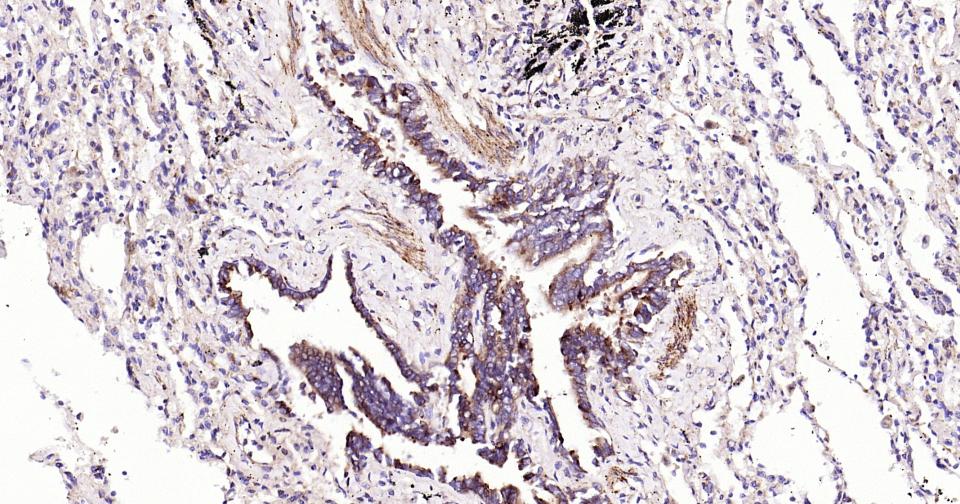

Paraformaldehyde-fixed, paraffin embedded Human Lung; Antigen retrieval by boiling in sodium citrate buffer (pH6.0) for 15 min; Antibody incubation with PIK3C3 Monoclonal Antibody, Unconjugated(bsm-61161R) at 1:200 overnight at 4°C, followed by conjugation to the SP Kit (Rabbit, SP-0023) and DAB (C-0010) staining.